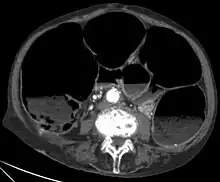

| CT-scan showing a coronal section of the abdomen of an elderly women with an IPO. | |